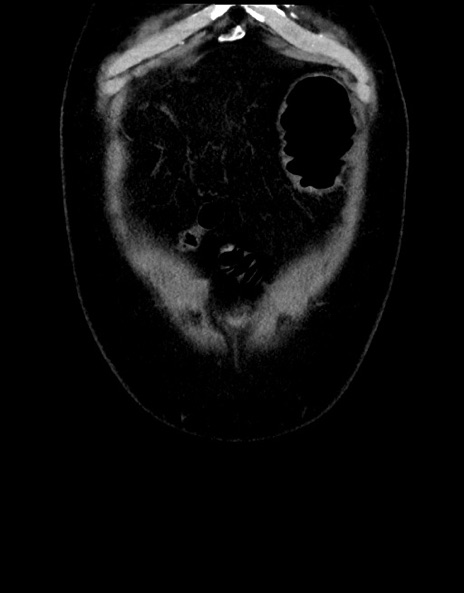

横断像

【症例】70歳代男性

【主訴】腹痛

【現病歴】今朝から腹痛あり。全体的に痛い。特に左上の方。排ガスが今日はない。冷や汗が出る。

【既往歴】直腸癌術後

【身体所見】左側腹部〜上腹部に圧痛あり。腹膜刺激症状明らかなではない。軽度反跳痛。左下腹部に術後瘢痕あり。

【データ】WBC 7700、CRP 0.02